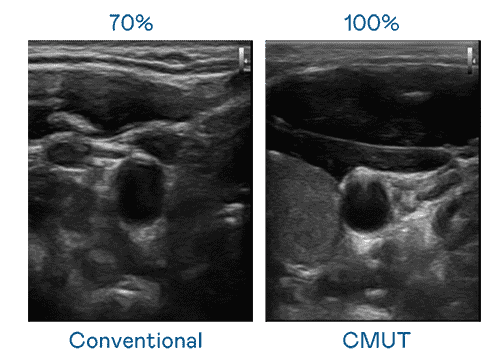

CMUT 技术是一种用电容式微机电元件来产生超音波讯号的技术。。。。与传统 PZT 压电式技术相比,,,,CMUT 频宽增加 30%,,,更宽频的超音波讯号让影像解析度大幅提升,,是实现高影像品质医疗超音波扫描、、、、促进精准医疗发展的关键技术。。

超音波影像的解析度高低,,首先取决于探头能发出的讯号频宽。。。z6尊龙 CMUT 可提供高清晰的超音波讯号,,,提供高频宽、、、、高灵敏度、、、、影像纹理细节更高的超音波影像,,协助医护人员缩短影像判读时间及利用精准的医疗影像进行诊断。。